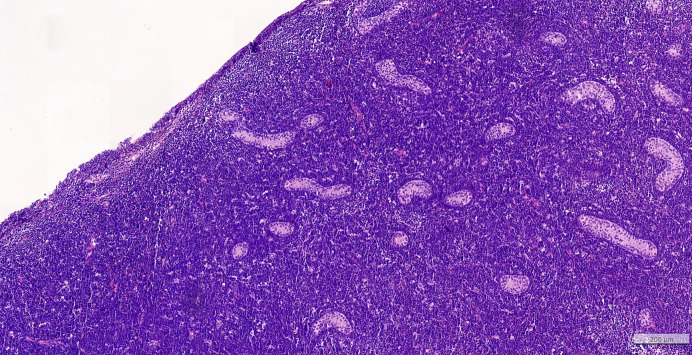

Introduction: Aleukemic leukemia cutis (ALC) is a rare condition and concerns less than 10% of leukemia cutis (LC) cases. LC is defined as a cutaneous infiltration of neoplastic myeloid or lymphoid blasts, which occurs in the absence of any prior bone marrow or peripheral blood involvement.

Case presentation: A pediatric case of B-cell ALL presenting as ALC is presented because of an exceptional testicular localization.

Conclusion: B-cell acute lymphoblastic leukemia presenting as ALC is rarely described in the literature, and this case could be the first of childhood ALC with testicular involvement.